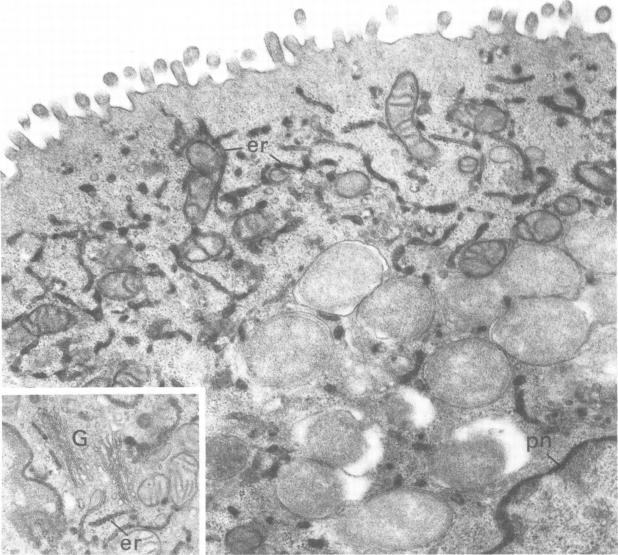

Guinea pig inclusion conjunctivitis, a naturally occurring chlamydial disease of guinea pigs, resolves spontaneously after 3 to 4 weeks. The factors responsible for curbing the infection have not yet been specifically defined. Since Iwata (Invest. Ophthalmol. 15:297-301, 1976) reported cytochemical activity for peroxidase in the conjunctival epithelium of the normal rat, we undertook these studies to determine whether a similar activity exists in the guinea pig, and if so, whether it functions in the elimination of this Chlamydia psittaci infection. Tarsal conjunctivas of 14 normal guinea pigs, 34 infected ones, and 7 control guinea pigs (inoculated with yolk sac only) were excised and tested for peroxidase by the Graham and Karnovsky method (J. Histochem. Cytochem. 14:291-302, 1966). We found that peroxidase activity, virtually absent in normal animals, was intensely stimulated by the infection. This enzymatic activity appeared 2 days after inoculation of the conjunctiva with chlamydia and persisted for 6 to 7 weeks. The enzyme was localized in the rough endoplasmic reticulum and perinuclear cisternae of all layers of the conjunctival epithelium from the external surface to the basal lamina, including cells with no apparent inclusions as well as those heavily parasitized. Reaction in the Golgi complex was variable. No reaction, however, was ever evident in the chlamydial vacuoles or lysosomes, and the organisms continued to grow and multiply during peak enzymatic activity. We therefore concluded that the stimulated enzyme is apparently not directly responsible for the waning of the infection, but instead reflects an alteration of host metabolism that occurs as a consequence of the infection.

豚鼠包涵体结膜炎是豚鼠自然发生的一种衣原体疾病,3至4周后可自发痊愈。抑制感染的因素尚未明确界定。自岩田(《Invest. Ophthalmol.》15:297 - 301,1976年)报道正常大鼠结膜上皮中过氧化物酶具有细胞化学活性以来,我们开展了这些研究,以确定豚鼠是否存在类似活性,若存在,其是否在消除这种鹦鹉热衣原体感染中发挥作用。切除14只正常豚鼠、34只感染豚鼠和7只对照豚鼠(仅接种卵黄囊)的睑结膜,采用格雷厄姆和卡尔诺夫斯基方法(《J. Histochem. Cytochem.》14:291 - 302,1966年)检测过氧化物酶。我们发现,正常动物几乎不存在的过氧化物酶活性在感染后受到强烈刺激。这种酶活性在结膜接种衣原体后2天出现,并持续6至7周。该酶定位于从外表面到基底层的结膜上皮各层的粗面内质网和核周池,包括无明显包涵体的细胞以及严重寄生的细胞。高尔基体中的反应各不相同。然而,衣原体空泡或溶酶体中从未出现明显反应,并且在酶活性高峰期病原体继续生长繁殖。因此,我们得出结论,受刺激的酶显然不是感染减弱的直接原因,而是反映了感染导致的宿主代谢改变。